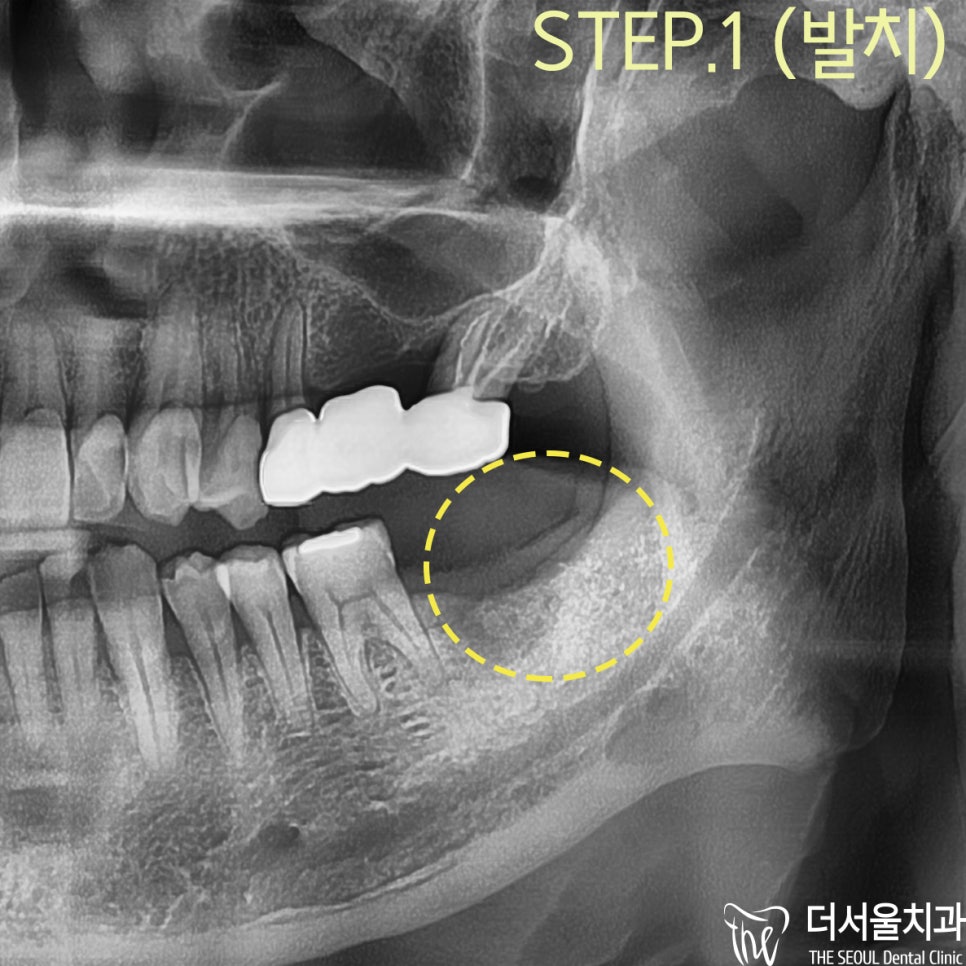

1. 37번 : 발치 후 픽스쳐 식립

2. 38번: 사랑니 발치

#38번 사랑니는

대합 되는 치아가 없어서

구강 기능을 전–혀 못하는 상황이었으며

치아 정출로

어금니 위쪽으로 솟아올랐는데

반대편 잇몸이 씹힐 가능성이 높았습니다.

이러한 이유에서

사랑니 발치를 계획하게 되었습니다.

먼저, 발치를 하고

수술 전 모의 수술을 통해서

픽스쳐가 심겨질 위치를 파악하게 되었습니다.

#37번

뿌리 끝에 염증이 있어서

부가적으로 뼈이식이 필요했던 상황이었습니다.